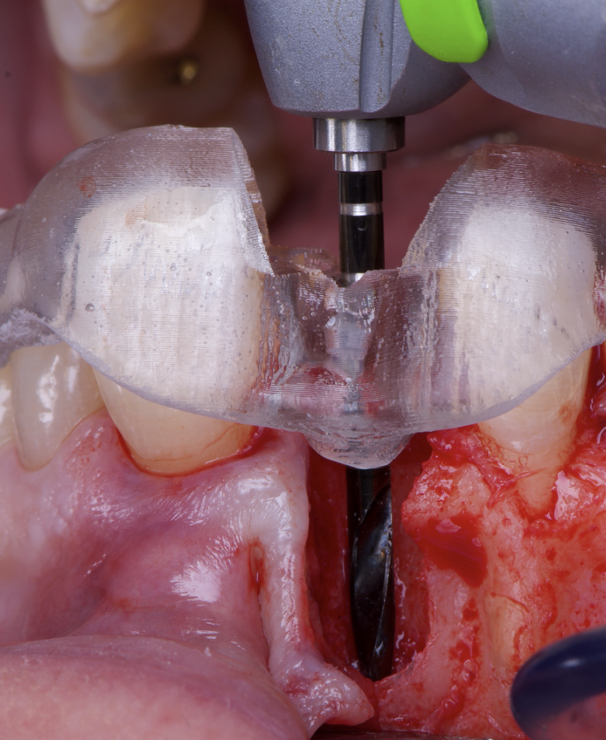

The surgical protocol began with the atraumatic extraction of tooth 1.1 to preserve as much of the alveolar socket as possible. Immediately following extraction, an N1 implant was placed into the socket using a guided surgical approach to ensure ideal three-dimensional positioning. The “one abutment one time” technique was applied to minimize soft tissue manipulation during the healing phase, which is particularly important in esthetic areas.